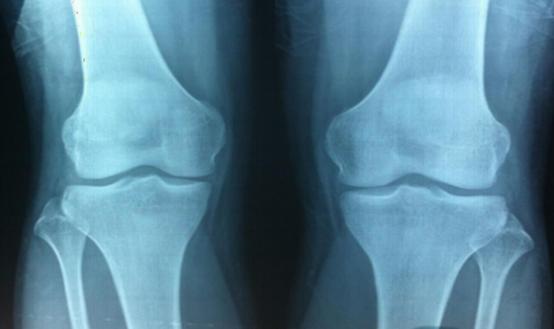

如果宝宝身高小于或等于-2SD,说明宝宝生长过于缓慢,可能是矮小症,此时需要及时就医,在医生指导下进行激素注射!

但是如果孩子身高已经属于矮小范围,一定要及时就医,在医生建议下,注射生长激素,同时搭配营养调理,才能事半功倍!此时营养仅仅为促进作用!主要治疗方式是激注射激素。

其实矮小症只要做到早发现、早诊断,是可以通过治疗达到正常身高的。孩子的年龄越小,骨骺的软骨层增生及分化越活跃,孩子生长的空间及潜力越大,对治疗的反应越敏感,药物促生长效果越好。但是如果孩子不属于矮小范围,不建议用生长激素来过度拔高!